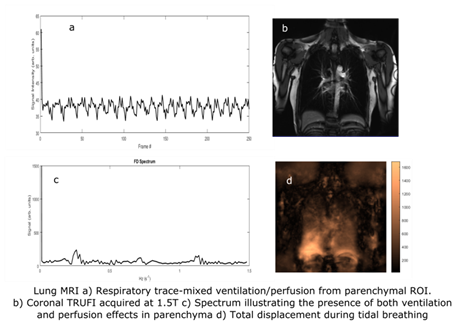

• developing lung ventilation and perfusion MRI techniques to assess severity of disease and treatment efficacy in respiratory diseases.

MRI-4